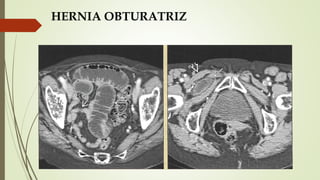

HERNIA OBTURATRIZ

Hernia pélvica que protruye a través del

agujero obturador.

 Evidencia por TC de intestino

herniado entre los músculos pectíneo

y obturador en mujeres de edad

avanzada

 > 90% en mujeres ancianas (80 años).

 < 1% de todas las hernias

 CX:

 Obstrucción aguda o recurrente del intestino delgado.

 Masa dolorosa en la región del obturador.

 Signo de Howship-Romberg: dolor en la zona medial del

muslo/cadera con la abducción, extensión, rotación

interna de la rodilla; la flexión alivia el dolor. (irritación

del nervio obturador)

 Signo del Hannington-Kiff: ausencia del reflejo aductor

en el muslo.

 RADIOGRAFÍA DE ABDOMEN O ESTUDIOS

BARITADOS:

 Obstrucción del intestino delgado con un asa fija que

contiene gas o medio de contraste en la región del

obturador.

 HALLAZGOS DE TC:

 Asa de intestino que protruye a

través del agujero obturador.

 Frecuentemente:

 Asa ileal.

 Atrapada entre los músculos

obturador externo y pectíneo.

 Lado derecho.